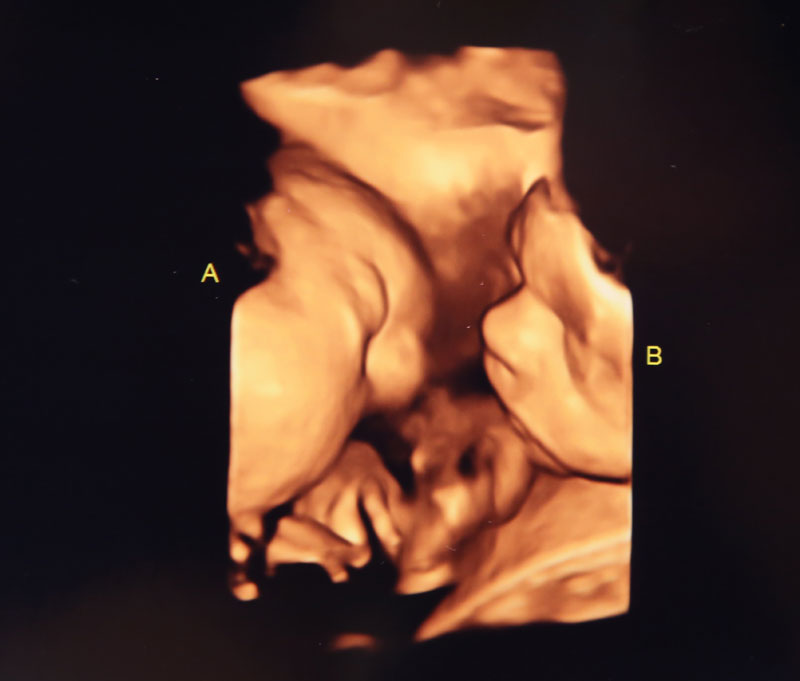

Barberic reports she’s seen kicks that look like dancing, especially with twins.

“I’ve seen legs moving, kicking and head flung back,” she said.

An Irish study revealed that babies move in reaction to sound as early as 16 weeks. This was earlier than previous estimates and before completion of the ear development, suggesting there is more to hearing than the ear alone.